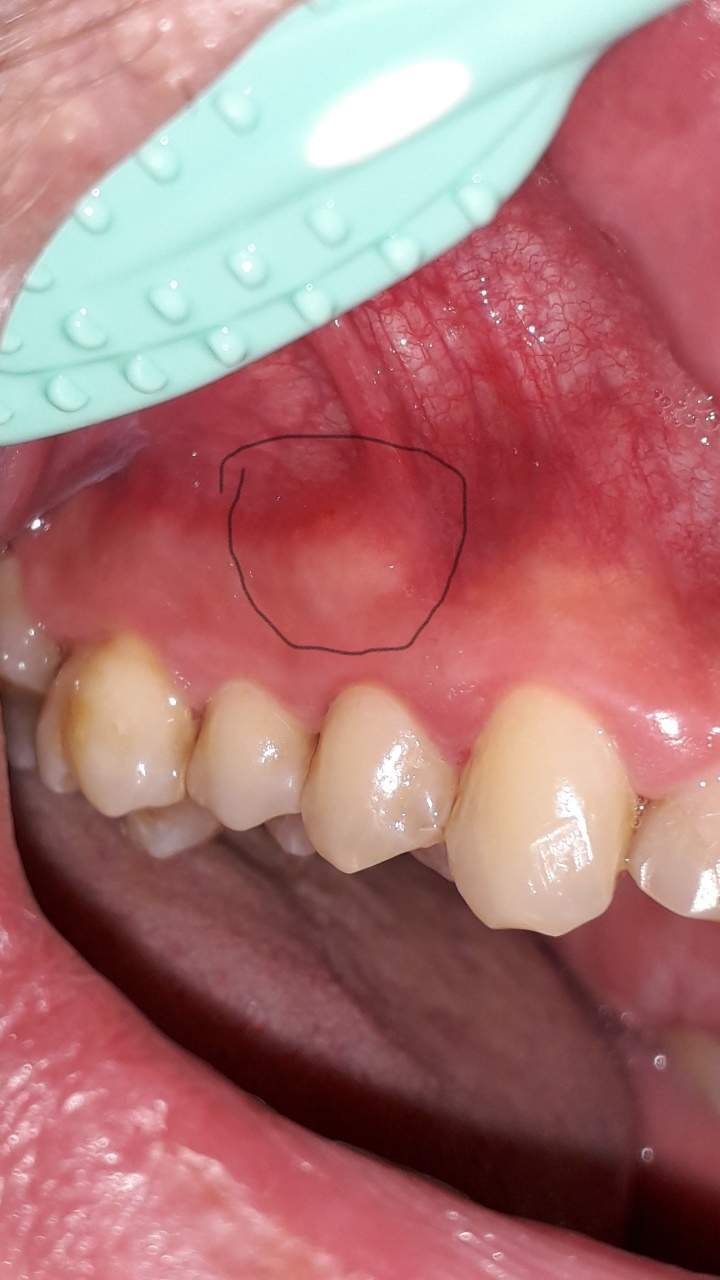

Eine Schwellung des Zahnfleisches ist ein Anzeichen für eine Entzündung. Hierbei wird Flüssigkeit im Gewebe eingelagert, welches durch eine Allergie oder Infektion hervorgerufen werden kann. Weitere Auslöser können sein: ein traumatischer Zahnunfall oder eine Verletzung. Ödeme. Blutungen. Fisteln am Zahnfleisch.. Auch eine Schwellung der betroffenen Areale (z. B. am Zahnfleisch, Gaumensegel, Gaumenzäpfchen, den Gaumenmandeln oder dem allgemeinen Oberkiefer) ist ein klassisches Entzündungszeichen. Begleitende Bläschen können auf einen Virenbefall oder Aphthen hindeuten. Gelbweiße Eiterherde weisen normalerweise auf eine Bakterienbesiedlung hin.

Schmerzlose Schwellung des Gaumens Behandlungsalgorithmus und Differenzialdiagnose

Ein geschwollener Gaumen bereitet nicht nur Schmerzen, sondern führt auch oftmals dazu, dass nicht mehr richtig gegessen werden kann. Es gilt daher, den geschwollenen Gaumen möglichst schnell zu behandeln und dadurch zu einer schnellen Genesung zu führen. Um zu verstehen, wie ein geschwollener Gaumen überhaupt entsteht, muss zunächst auf die Ursachen. Um diese soll es […]. We accept most insurance, Worker's Compensation and affordable payment plans so financial concerns won't stand in the way of getting the care you need. Call us at (304) 263-4927 or email us today to schedule an appointment and take the first step on your journey to optimal health.